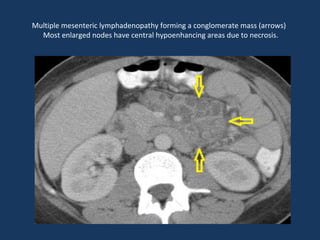

Multiple mesenteric lymphadenopathy forming a conglomerate mass (arrows)

Most enlarged nodes have central hypoenhancing areas due to necrosis.

Multiple mesenteric lymphadenopathyforming a conglomerate mass (arrows) Most enlarged nodes have central hypoenhancing areas due to necrosis.